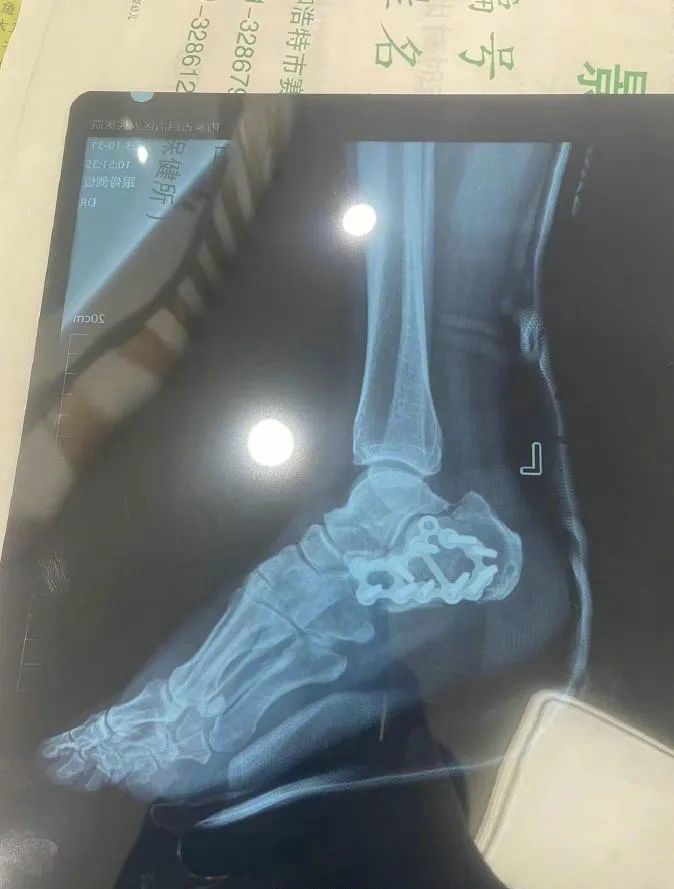

“那時候我剛工作了兩天,在第三天10月22日下午施工過程中從三層高的鐵架上摔了下來,導(dǎo)致30厘米左右的鋼筋刺穿我的右側(cè)臀部,左腳跟也粉碎性骨折,被送往內(nèi)蒙古自治區(qū)人民醫(yī)院救治,當晚做了手術(shù)取出刺在右臀部的鋼筋,10月30日又進行了左腳粉碎性骨折手術(shù)?!崩紫壬嬖V記者。